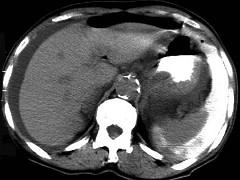

问题 男,44岁,突然中上腹痛,压痛,反跳痛,腹肌紧张,发热,白细胞计数升高,CT检查如图,最可能诊断是 ( )

选项 A.急性胰腺炎 B.慢性胰腺炎 C.胃小弯溃疡穿孔 D.胰腺癌 E.胃癌

答案 C